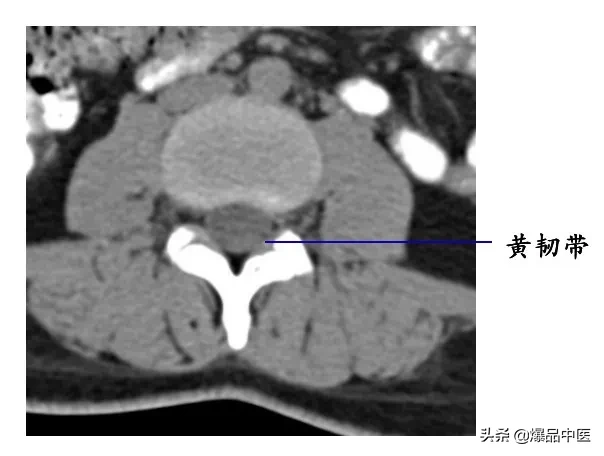

在相邻椎骨的椎弓之间的叫椎弓间韧带,由弹性结缔组织构成,呈黄色,故又称黄韧带。

后壁:椎板、黄韧带

黄韧带较厚(正常时≤3 mm),位于椎板和关节突的内侧面,密度高于硬脊膜囊和硬膜外脂肪,显示较清晰